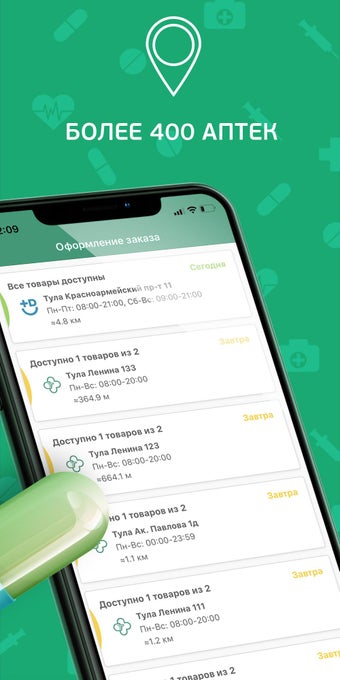

- Tìm kiếm các loại thuốc trong tất cả 790+ nhà thuốc của mạng lưới của chúng tôi

- Đặt thuốc từ bất kỳ nhà thuốc nào của chúng tôi

Bạn có thể sử dụng ứng dụng để tìm kiếm các loại thuốc không có sẵn trong nhà thuốc của bạn, đặt hàng giao hàng đến nhà của bạn hoặc đặt hàng từ một nhà thuốc gần bạn.